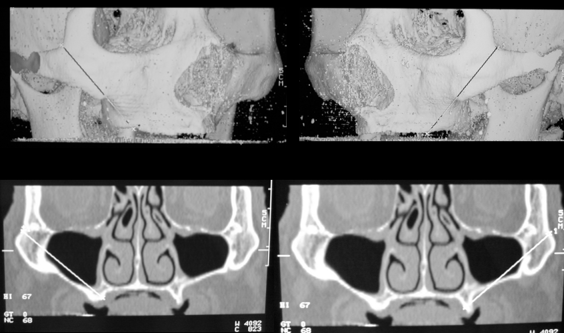

The zygomatic implant averages about 50mm long compared with the regular implantwhich ranges from 7mm to 15mm. This is because the bone supporting the implant is the zygoma bone ie the cheek bone and not the jaw bone. This implant enters the upper jaw, traverses the maxillary sinus and enters the zygoma bone with forms the outer roof of the sinus. This technique was introduced more than ten years ago but has not been popular until recently. More data has emerged, showing the success rates of zygomatic implants to be on par with regular implants, and has spurred a new interest in the system.

Studies in the last few years have shown that it is possible to placed two zygoma implants on each side, ie having four zygomatic implants to support a fixed prosthesis. The data showed that success for this protocol is similar to that of regular implants. It has the added advantage of immediate restoration with a functional prosthesis, thereby shortening the treatment duration.